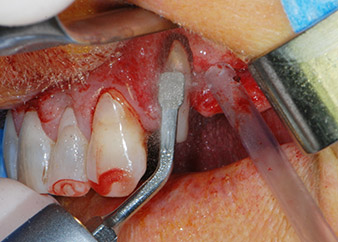

One month later, on the day of surgery, pain and inflammation at tooth 24 were minimal, but mobility of Miller class 2 was still present. After opening the flaps and cleaning the periapical and peri radicular infected tissue, the extent of the bone defect became obvious (Figs. 2 and 3).

At the buccal root, all vestibular and distal bone was missing. Attachment was essentially restricted to the palatal root, underlining the preliminary poor prognosis. Tooth 27 also showed a reduced horizontal attachment and a minimal apical rarefaction (cf. Fig. 1) without clinical symptoms.

total loss of bone and attachment

Fig. 2 and 3: After raising flaps, one month after endodontic revision and initiation of full-mouth periodontal therapy, the buccal root of tooth 24 showed a total loss of bone and attachment.

However, we maintained our initial plan to retain both teeth as temporary bridge abutments during the six-months osseointegration period of the implants. At reentry, the situation would have to be reassessed. First, in an attempt to manage the endo-perio problem, the remaining root surface was carefully debrided with piezoelectric equipment (Piezomed, W&H, used with the spatula-shaped insert S1, originally designed for erosion of the lateral sinus wall) (Fig. 4).